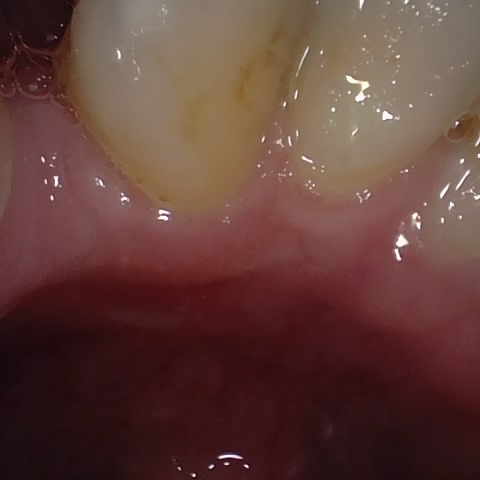

Annotated as "Bad"